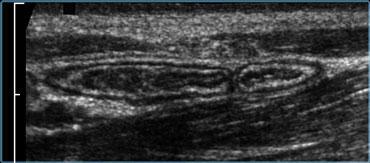

Ruột thừa bình thường có hình ảnh là một cấu trúc nhỏ, dễ đè xẹp, có các lớp đồng tâm, di động, tận cùng mù, hình ống dài như xúc xích.

Đường kính lên đến 7mm được coi là bình thường.

Ruột thừa bình thường có thể di động, lòng ruột có thể xẹp, nhưng cũng có thể chứa khí hoặc một ít chất phân, và hiếm khi chứa một ít dịch (6).

Doppler năng lượng cho thấy tín hiệu mạch máu thưa thớt hoặc không có, và không có lớp mỡ viêm tăng âm, không thể đè xẹp xung quanh ruột thừa.